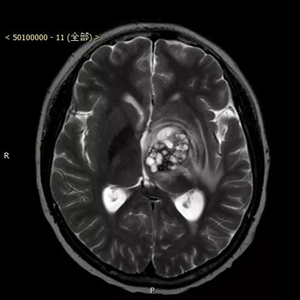

患者,男,入院时间2016年8月9日,入院时年龄13岁5月24天。主诉:右腿晃动3个月,伴右侧肢体力量减弱2个月。术后病理显示为囊性成熟型畸胎瘤,肿瘤组织内神经胶质细胞成分、平滑肌及腺上皮成分细胞异质性明显。

患者来到北京儿童医院就医时,由于肿瘤压迫脑功能区导致了瘫痪。北京儿童医院神经外科葛明教授及团队,对其进行了全切除手术,肿瘤直径4公分左右,手术路径深十公分左右,分块切除,历时四小时完整切除。术后患者瘫痪状态消失,随访恢复良好。

患者术前资料(下图)